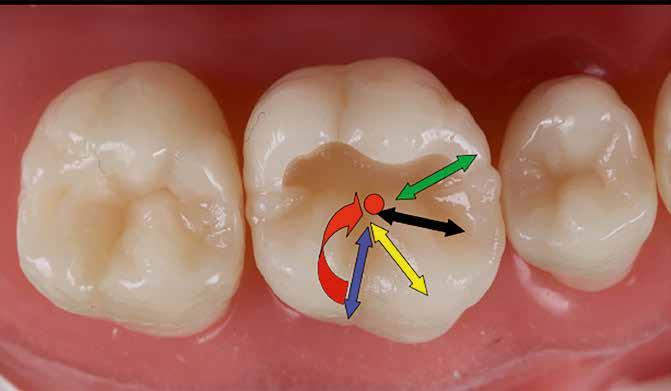

Posselt az állkapocs funkcionális mozgásait a mandibula határmozgásainak görbéjével (Posselt-féle diagram) írta le, amely három térbeli síkra bontható (1. ábra): sagittális, frontális és horizontális. Ebből következik, hogy a fogak dinamikus kölcsönhatása is három dimenzióban értelmezhető [7].

Az egyes csücskök háromdimenzóban végzett, funkcionális mozgáspályáinak összességét nevezzük okkluzális iránytűnek (2. ábra). Az okkluzális iránytű minden csücsök esetében egyedi (a rajta lévő bemélyedések és kiemelkedések szempontjából), és azt a csücsöknek a mandibula condylusának forgásközéppontjához viszonyított helyzete határozza meg.

Az okkluzális iránytű leírásához használt terminológia a The Glossary of Occlusal Terms-ből származik, amelyet a The Glossary Committee of The International Academy of Gnathology állított össze [8]. Fontos megjegyezni, hogy a mandibula mozgásai rágás és nyelés során mindig a maximális interkuszpidációs helyzetből indulnak ki, és oda is térnek vissza.

Ezek a mozgások a következők:

• PROTRUSIO (fekete) – az állkapocs előrefelé irányuló mozgása;

• LATEROTRUSIO (kék) – oldalirányú vagy kifelé történő mozgás;

• LATEROPROTRUSIO (sárga) – kifelé és előre irányuló mozgás kombinációja;

• LATERORESURTRUSIO (piros) – kifelé, hátrafelé és felfelé irányuló mozgás. Ez a mozgás Bennett-mozgásként ismert, Norman G. Bennett (1870–1947) után elnevezve;

• MEDIOTRUSIO (zöld) – mesiális oldalirányú, befelé történő mozgás, amely lehetővé teszi az ellenkező oldali condylus lefelé/előre irányuló mozgását [9].

Az iránytű középpontja (az IKP-ben létrejövő érintkezés) körül található egy kisebb szabad zóna, amely lehetővé teszi az antagonista csücsök mozgását a „hosszú centrikus” (Long Centric vagy Freedom in Centric) tartományban [10]. Ez képezi a Polz-féle biomechanikai wax-up [11] alapját, amelyre a DeVreugd-féle okkluzális iránytű is épül. Jelen publikáció célja egy dinamikus alapú, ésszerű megközelítés bemutatása a hátsó fogak direkt kompozittal történő restaurálásához, amelynek eredményeként a rétegezést követően csupán minimális utólagos korrekcióra van szükség. A szerző a rövidebb, lényegre törő bemutatás kedvéért a felső első molárisra fókuszál. Ezt a fogat azért választotta, mert rágás közben ez viseli a legnagyobb erőbehatást, és ezen a fogon található a legtöbb okklúziós érintkezési pont [9].

DeVreugd-féle okkluzális iránytű.

2. ábra: